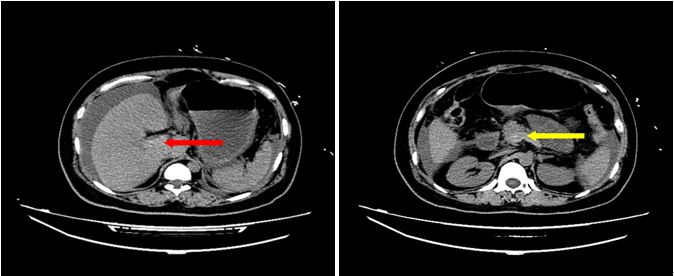

大概半小时后电脑系统上传回了CT的图像和报告 (见图 A):

1.腹腔积液;

2.脂肪肝可能;

3.门静脉及其属支密度略增高并小肠壁广泛增厚:门静脉系血栓待排;

4.胆囊术后缺如;

5.孕期子宫。

门静脉系统居然有血栓?那么肠道静脉回流肯定受影响,继而肠壁水肿、肠内菌群移位,导致腹腔感染,再发生脓毒性休克?这会不会就是患者发病机制呢?

图A腹部CT平扫(2018.04.14):门静脉、脾静脉密度增高(红色箭头代表门静脉、黄色箭头代表脾静脉)